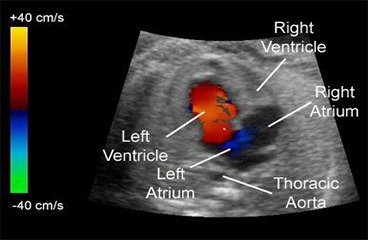

2D Echo, Color Doppler

2D Echo with colour doppler